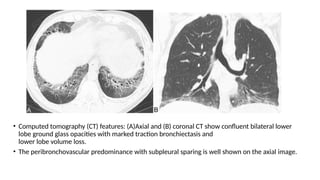

• Computed tomography (CT) features: (A)Axial and (B) coronal CT show confluent bilateral lower

lobe ground glass opacities with marked traction bronchiectasis and

lower lobe volume loss.

• The peribronchovascular predominance with subpleural sparing is well shown on the axial image.

• Computed tomography(CT) features: (A)Axial and (B) coronal CT show confluent bilateral lower lobe ground glass opacities with marked traction bronchiectasis and lower lobe volume loss. • The peribronchovascular predominance with subpleural sparing is well shown on the axial image.